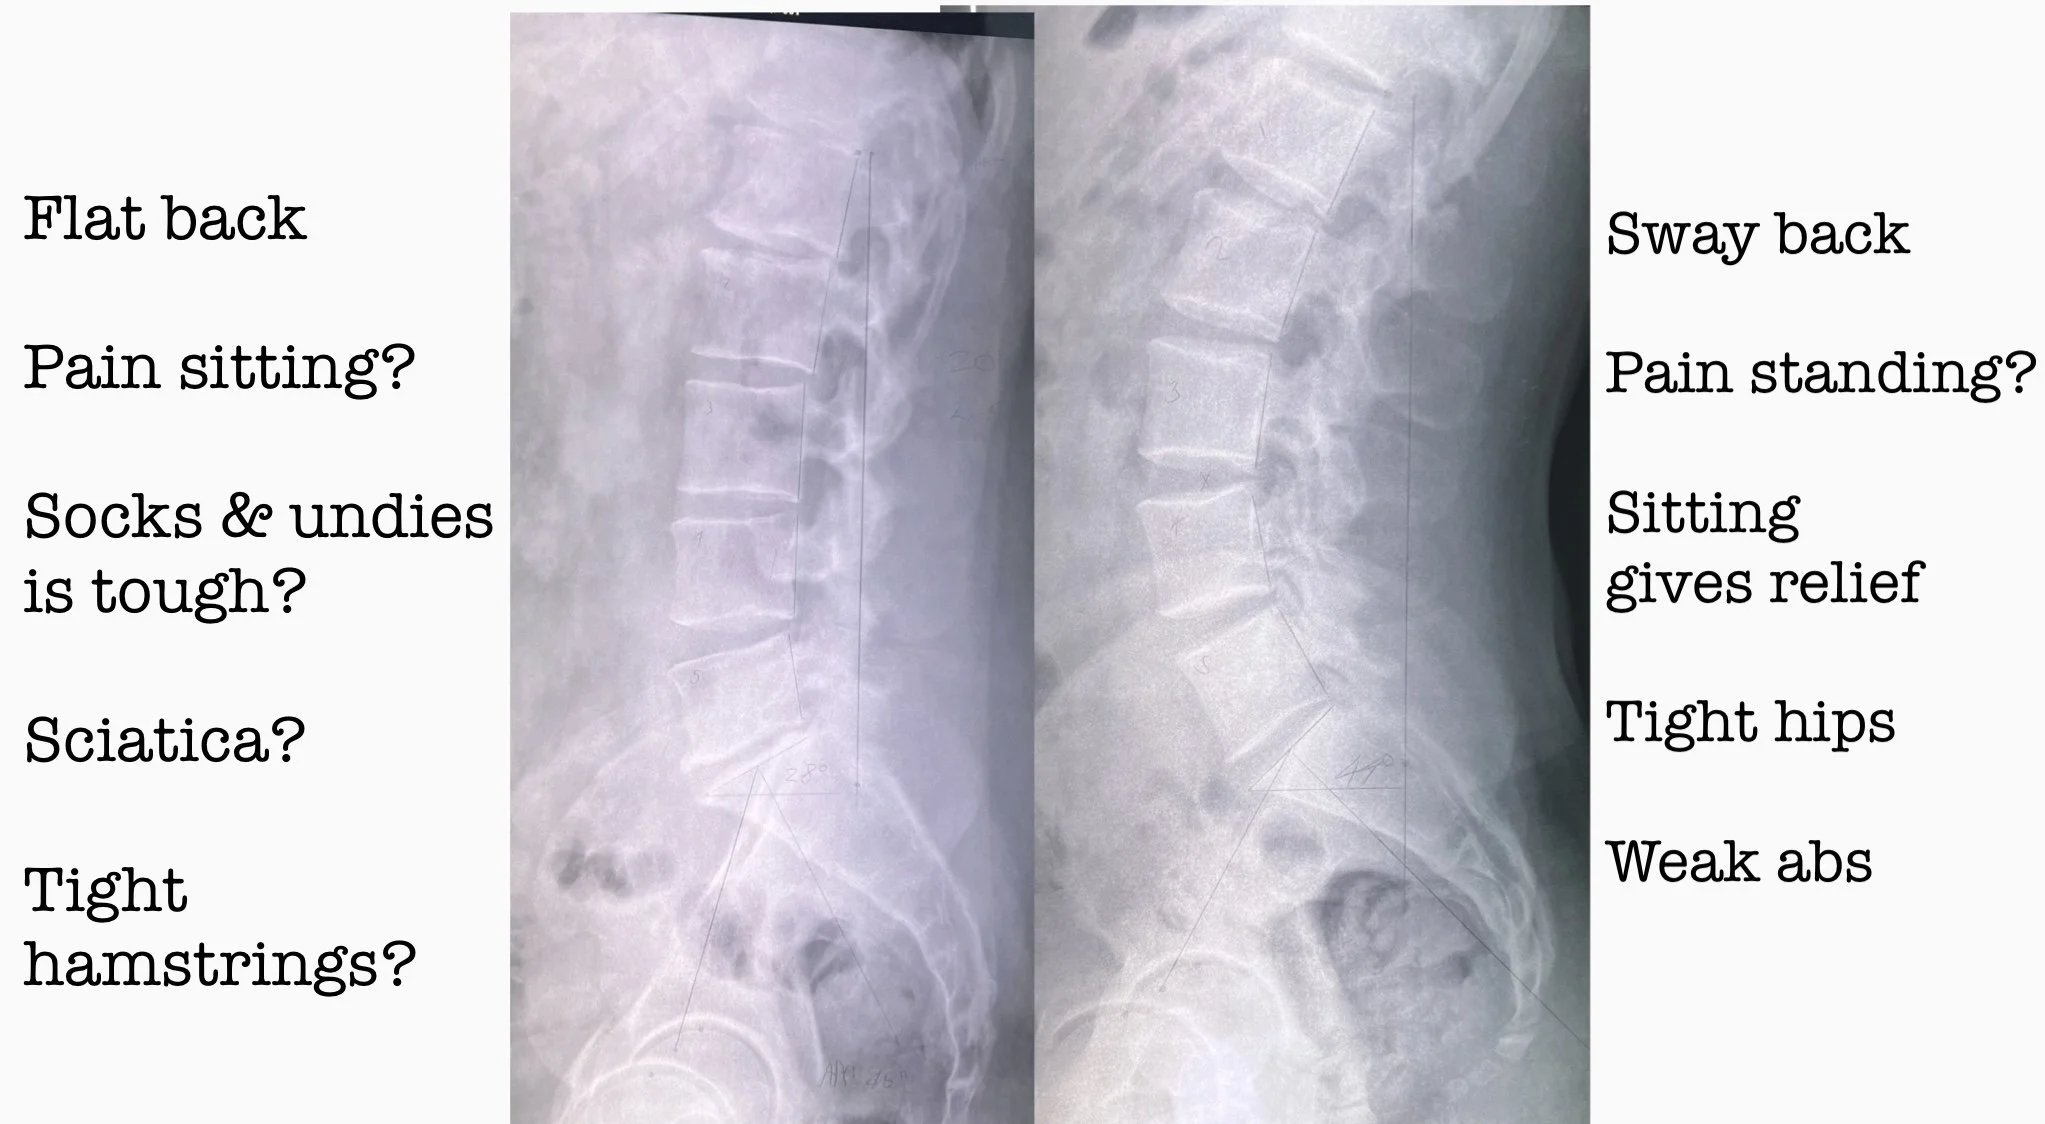

Do you feel 100 years old getting out of bed? How do you go putting on socks and underwear? Does prolongEd standing leave you tired and achy? Or perhaps its sharp sciatic Pain down The back of your legs?

There are many different types of low back pain and treatment for low back pain needs to be specific to be effective. Getting the diagnosis right is imperative.

X-rays reveal how your spine varies from normal alignment.

Once we know the exact alignment of your spine, the postures and movements that aggravate and relieve your low back pain will be very clear. This informs us as to the specific adjustments, exercises and postural corrective strategies that will be most useful for your low back pain treatment.